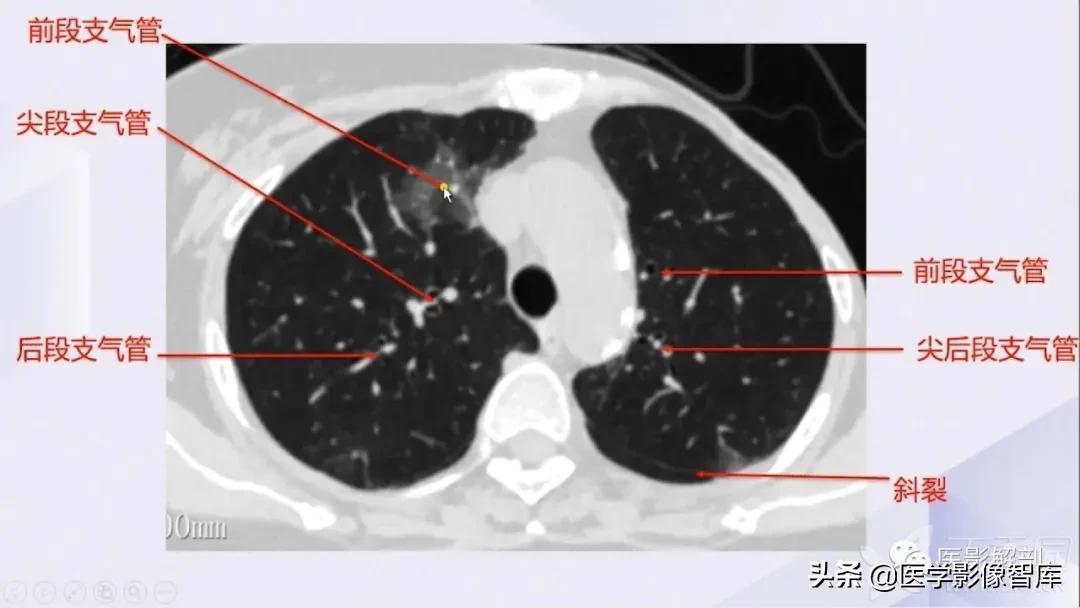

肺部CT解剖(高清图谱)